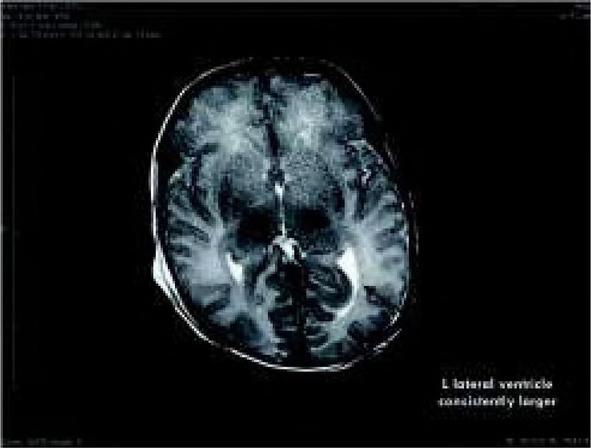

Fig. 5

Brain MRI of the patient, arrow points to the affected left side.

Ryc. 5. MRI mózgu pacjenta, strzałka wskazuje na uszkodzoną lewą stronę.